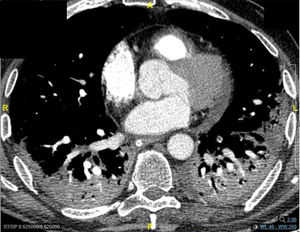

Pneumomediastinum (PM) is a condition where the air is present in the mediastinum. Free air leaks from ruptured alveoli, dissecting along the bronchovascular sheaths towards the mediastinum. PM, as seen on chest CT, elevates the mediastinal pleura and can extend into the neck or chest wall.14 One of the first signs that simulate a pneumomediastinum is the Mach band effect. This optical effect at the margin between areas of faintly different density15 can mimic various other pathologies (pneumopericardium, fracture), and makes it possible to suspect PM in COVID-19 patients. Non-traumatic PM is a rare complication of COVID-19 pneumonia.16 Its development in COVID-19 infection is also considered a possible indicator of disease worsening, which may be or not be associated with invasive ventilatory support. Spontaneous PM seemed to be a frequent complication of severe acute respiratory syndrome (SARS).17 In 2004, a high peak LDH level of 863 IU/L had been correlated with spontaneous PM in SARS patients, likely due to significant remodeling of the lung tissue causing leakage and vessel wall dissection.17 Most patients with PM had lung involvement higher than 50% at the moment of the diagnosis,18 corroborating the increased risk of rupture and PM development. This study aimed to evaluate the association between baseline serum LDH levels and COVID19 lung necrosis outcome based on the extent of lobar involvement and PM development.

In our study, CT was used to identify and confirm spontaneous PM and PM relative to mechanical ventilation. The scannographic signs of PM relied on the anatomical region occupied by the air as it exits the mediastinum.20 (Figs 1, 2).

GGO occupied 26% (8%–44%) of the lung area on baseline chest CT and 40% (14%–66%) on follow-up. Lobar consolidation was found in 38 (8.4%) patients on baseline chest CT and 30 (14.3%) patients on follow-up. Follow-up chest CT showed a higher number of patients with PE and PM than on admission: PE was found in 3 (0.7%) on admission versus 10 (4.8%) patients on follow-up, noting that a contrast chest CT was only done in case of high suspicion of PE. Two (0.4%) patients presented a PM on admission, and 12 (5.7%) had PM on follow-up. A mixed pattern was detected in 21 (4.5%) patients on admission chest CT.

Of the total sample, 2.7% had PM on CT (Table 1), of which 1.35% were ventilated/intubated, and 1.35% had a spontaneous PM.

In our series, 14 patients presented with PM, of whom, 7 had spontaneous PM. Among those, 2 had PM at baseline chest CT and 5 on follow-up chest CT. The follow-up chest CT done after a median of 16 days (Q1=11.5–Q3=21.5) showed that 8 patients intubated with a control plateau pressure presented a PM, of whom, 7 developed PM post-intubation, with a median of 7 days (Q1=2–Q3=18).